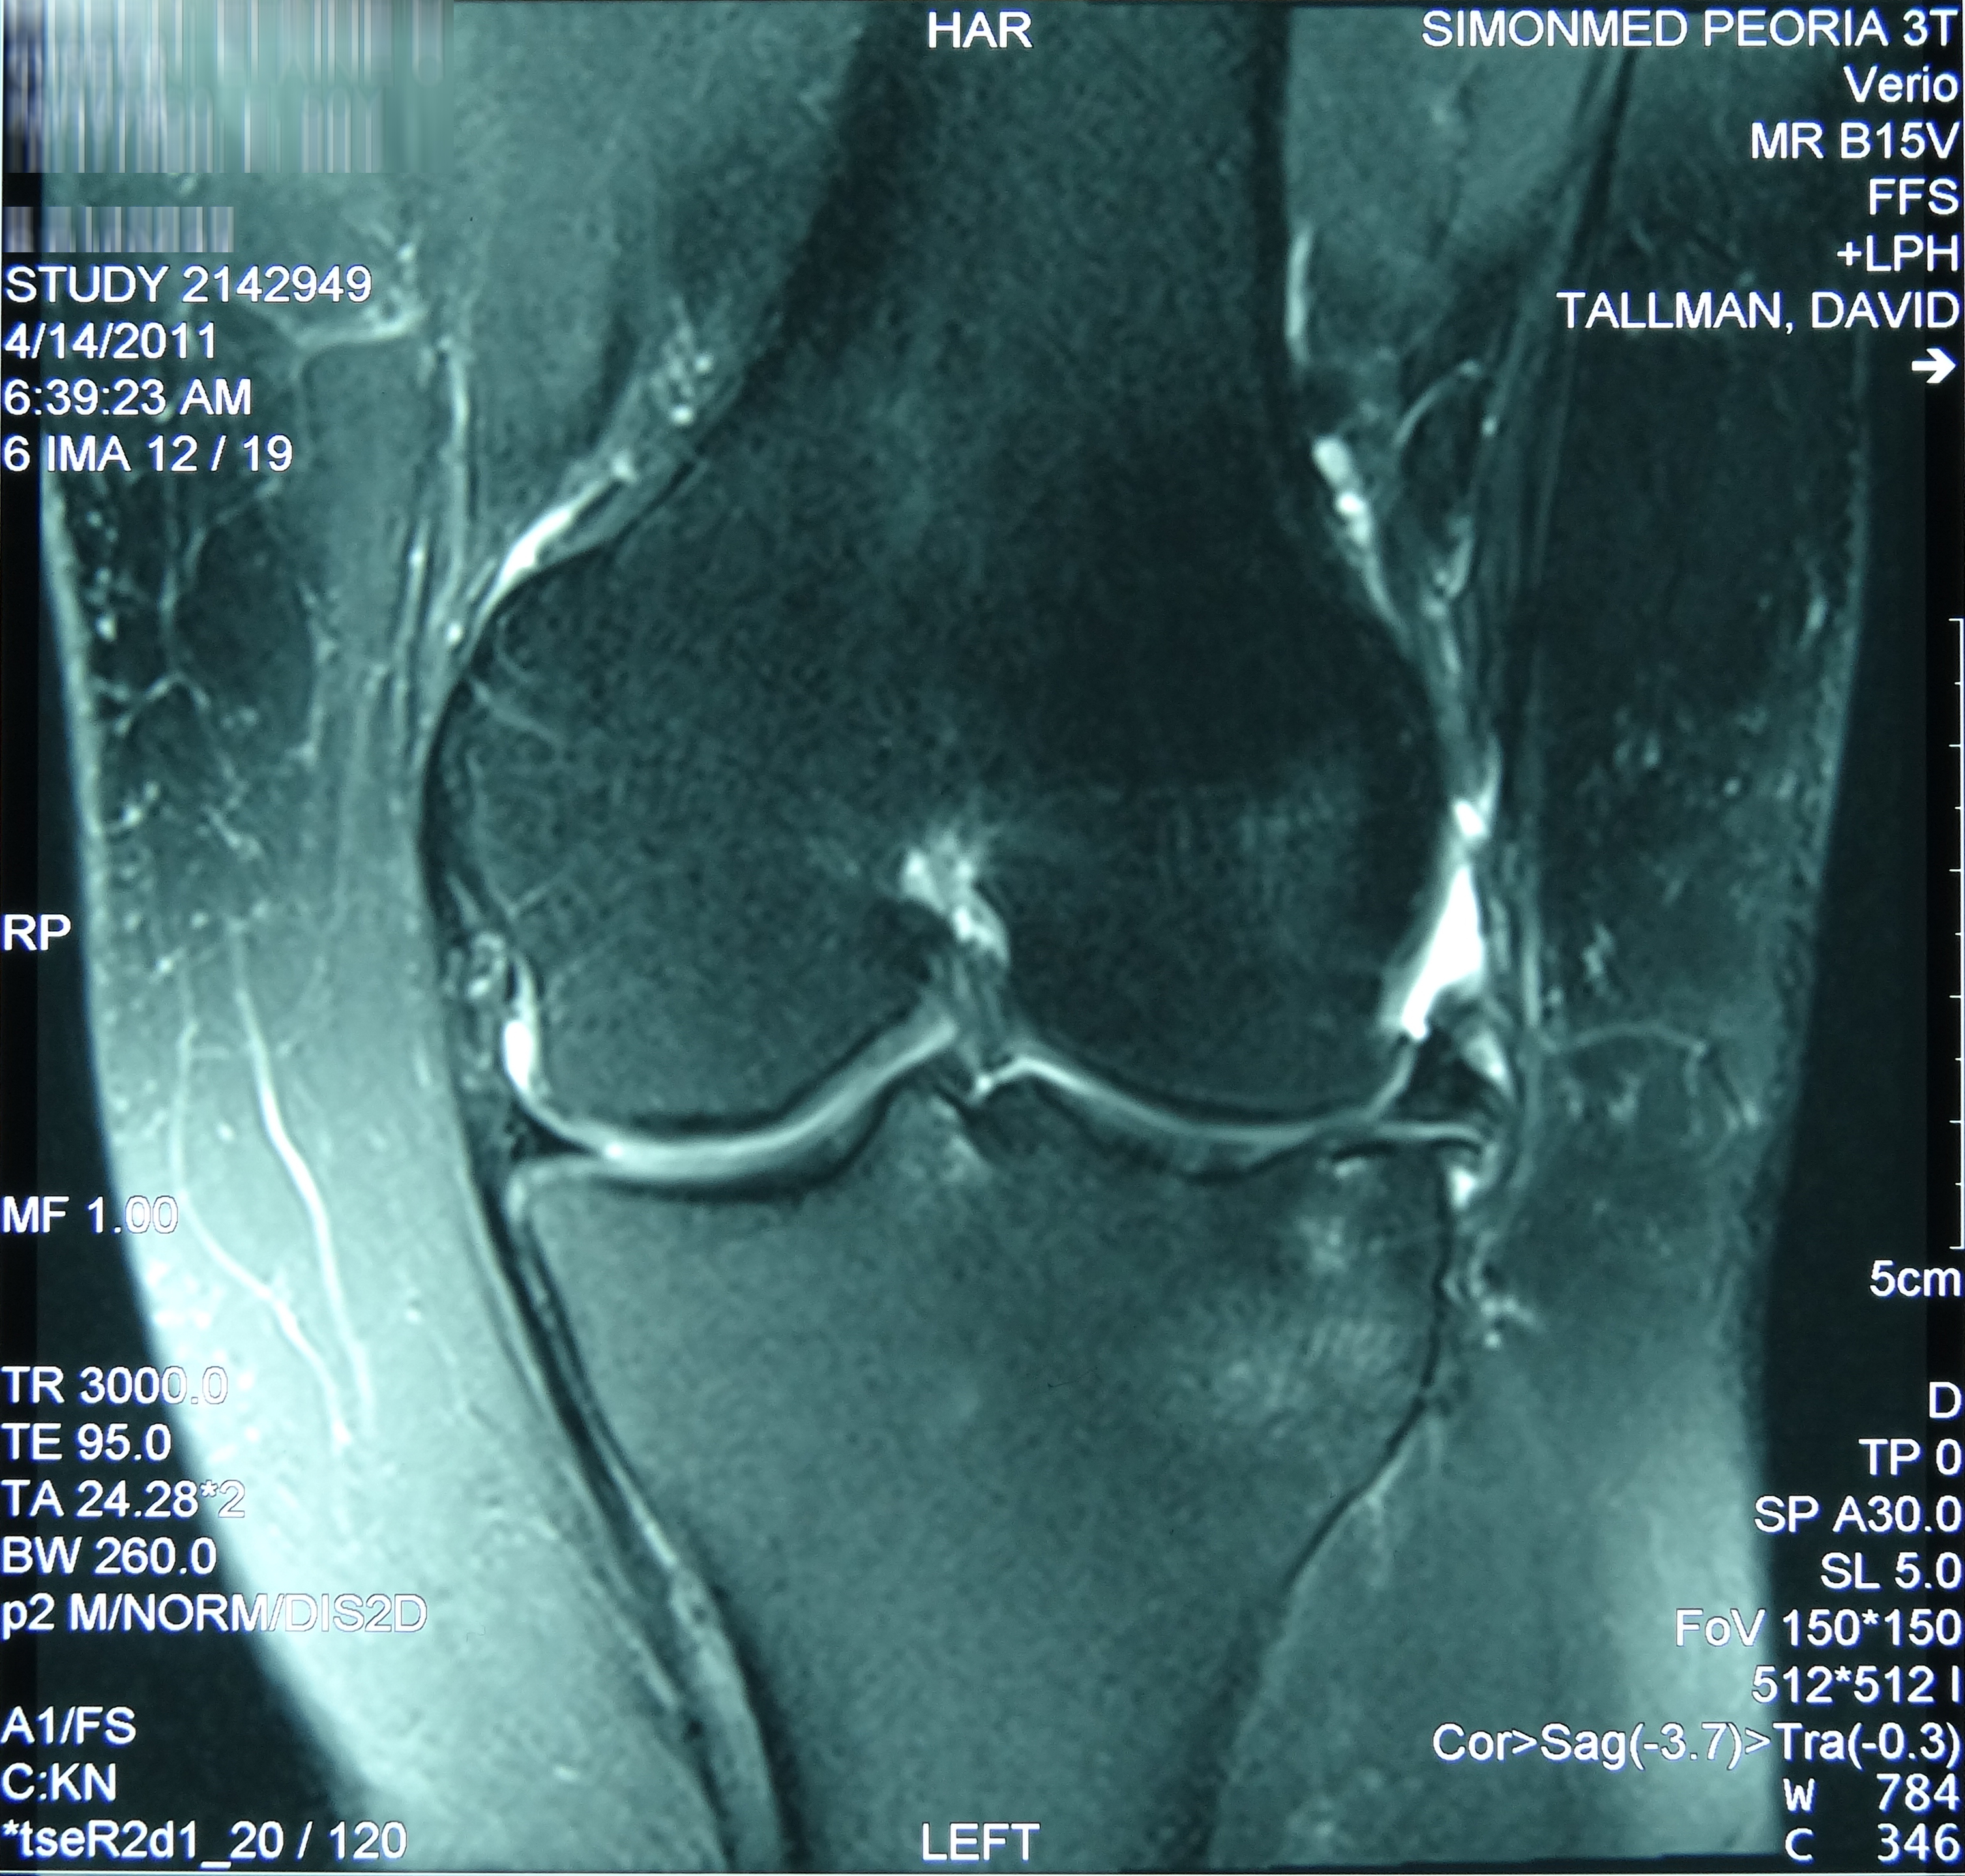

This patient presented with an ultrasound demonstrating a baseball-sized Baker's cyst behind the knee. The "after" film was taken 4 months after the 8th treatment of prolotherapy. He is now enjoying being pain and Baker’s cyst free. At three year follow-up, the cyst had not returned.[/toggle_content]